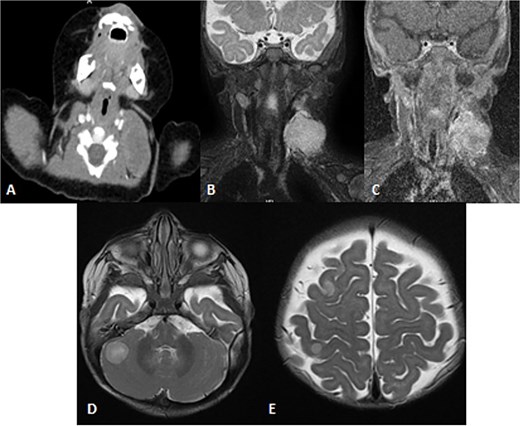

To achieve local control, surgical management using hemipelvectomy was suggested based on the lesion’s size and progression. However, this option was refused by the family. The patient was then started on chemotherapy. Whole body staging MRI did not show any metastatic lesions. After 3 months of treatment, the patient started having generalized seizure episodes. Brain neuroimaging with computed tomography (CT) scan showed an isodense mass in the posterior fossa, which was causing tonsillar herniation and obstructive active supratentorial hydrocephalus (Fig. 4). Goals of care were determined and the patient was transitioned to comfort care, after which she passed away.

Patient underwent brain CT after presenting to the ER due to seizure. (A and B) Sagittal and axial nonenhanced brain CT shows an isodense mass in the posterior cranial fossa with scattered areas of hyperdense foci denoting a hemorrhagic component that is completely effacing the fourth ventricle, causing supratentorial ventricular dilatation and periventricular hypodensity denoting cerebrospinal fluid (CSF) permeation indicating an active obstructive hydrocephalus. Also noted bilateral tonsillar herniation.